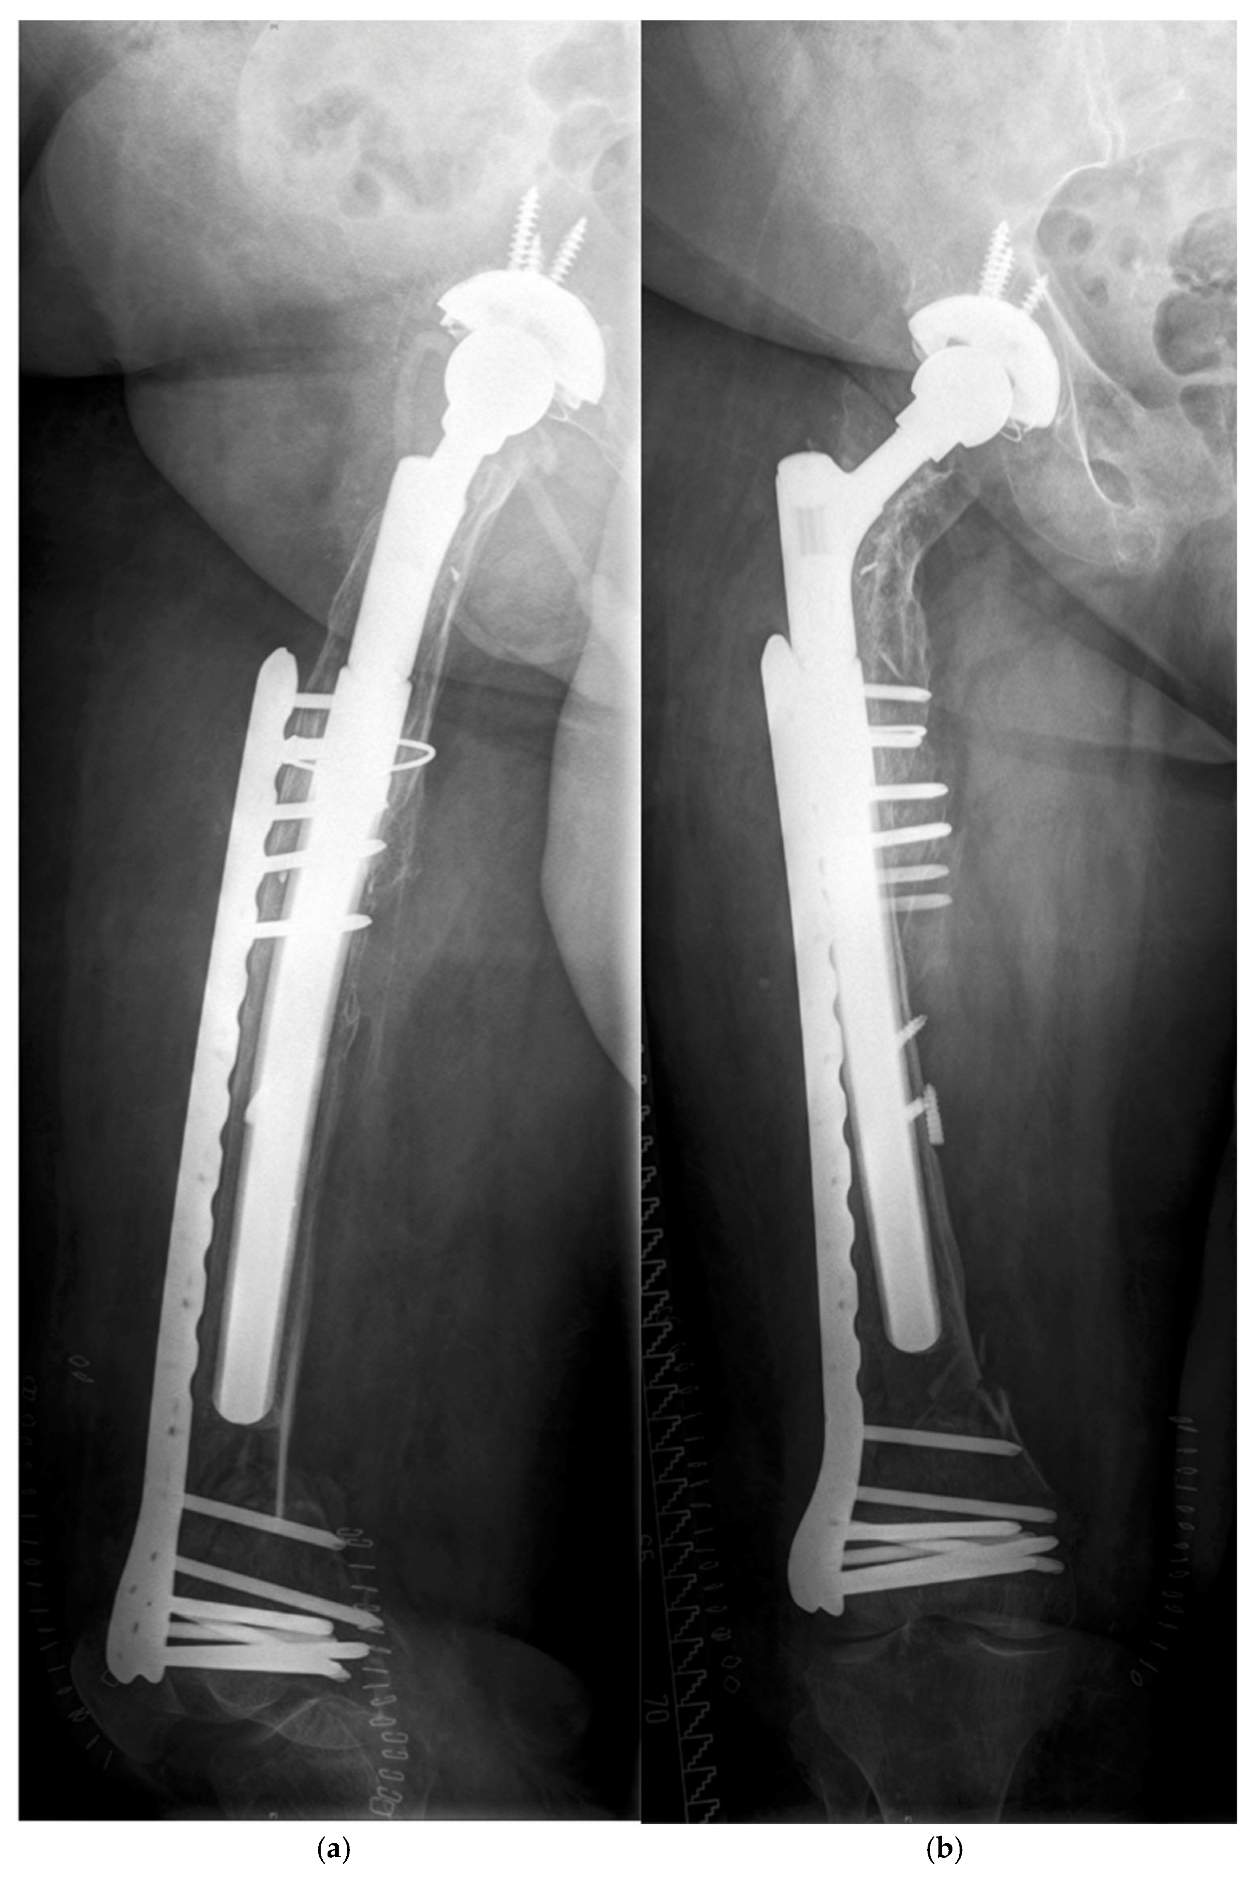

| 77, f. | TSR | 4 | TG | 20.8 | y | 4.2 | C | O (ORIF by Plate) | 290/14 |

| 68, f. | AL | 2B | TG | 22.5 | n | 0.8 | C | O (ORIF by Plate, Liss ©) | 250/18 |

| 73 +, f. | AL | 3B | TG | 34.4 | n | 8.6 | C | O (MIS by Plate, VA ©) | 290/21 |

| 75, f. | AL | 2B | TG | 25.9 | n | 9.8 | C | O (ORIF by Plate, VA ©) | 250/19 |

| 76, f. | AL | 2A | TG | 31.8 | n | 0.1 | B1 | O (ORIF by Plate, Liss ©) | 240/22 |